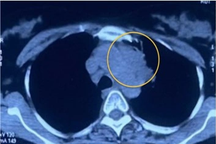

Tại đây, bệnh nhân được cắt lọc, dùng kháng sinh, dùng kỹ thuật hút áp lực âm (VAC) để xử lý tình trạng nhiễm trùng tại các ổ loét. Đáng chú ý, qua kết quả xét nghiệm và chẩn đoán hình ảnh, ekip điều trị phát hiện bệnh nhân có khối u tủy sống đã di căn xa đến gan, phổi, khiến tính mạng bị đe dọa nghiêm trọng.

Bác sĩ cho biết, khối u tủy của bệnh nhân B. đã di căn xa, rất khó khăn để điều trị (Ảnh: Hoàng Lê).